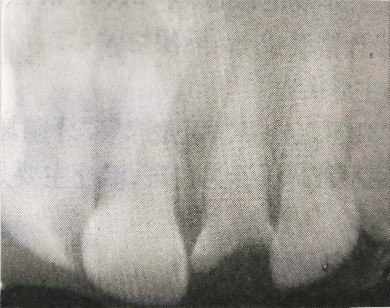

檢查:21牙冠缺損,黑褐色,根管口暴露,覆蓋污穢物,探診(-),冷測(cè)(-),叩診(+)。左上1唇側(cè)牙齦根尖部有白色瘺管出現(xiàn)。X線(xiàn)片檢查提示:21根尖區(qū)低密度影。全口牙齦紅腫,探診后出血,且下頜后牙區(qū)有附著喪失。相關(guān)情況請(qǐng)見(jiàn)下圖:

(3)X線(xiàn)檢查示21根尖部陰影。